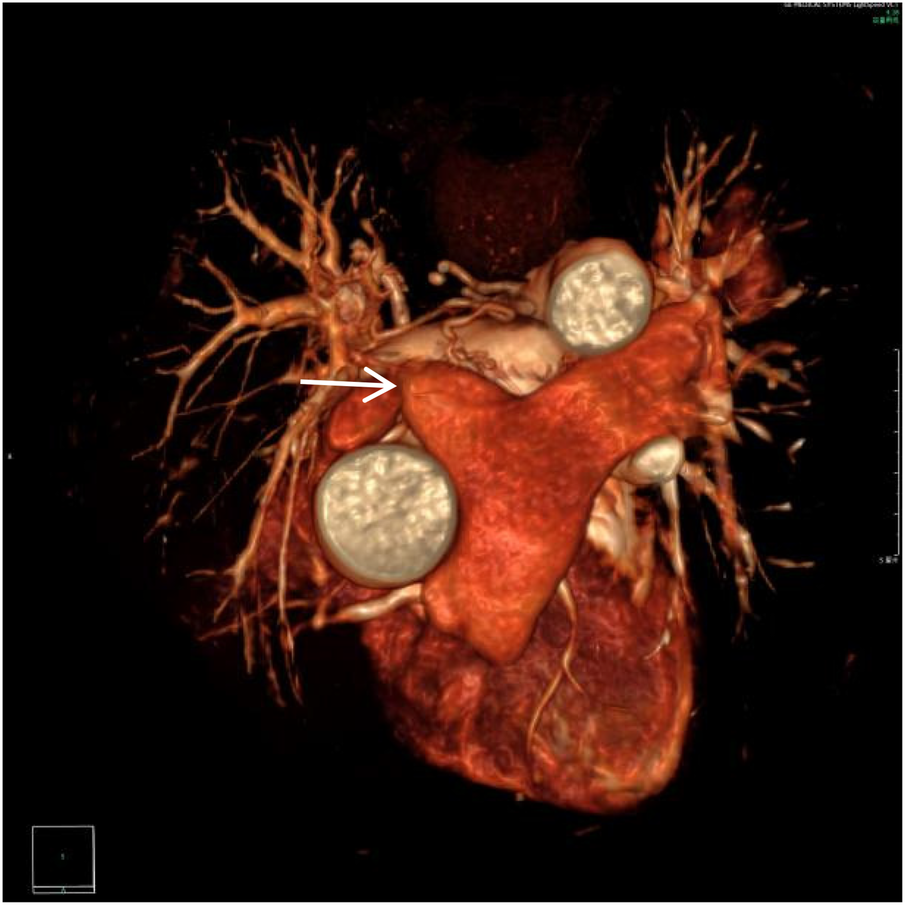

Figure 1

VR image shows absence of the distal main right pulmonary artery, with a rounded and blunt stump (white arrow).

Figure 2

CTA axial image shows absence of the distal right pulmonary artery, with a rounded and blunt stump (white arrow). No abnormal density shadows are observed within the main pulmonary artery and the proximal segments of the left and right pulmonary arteries.